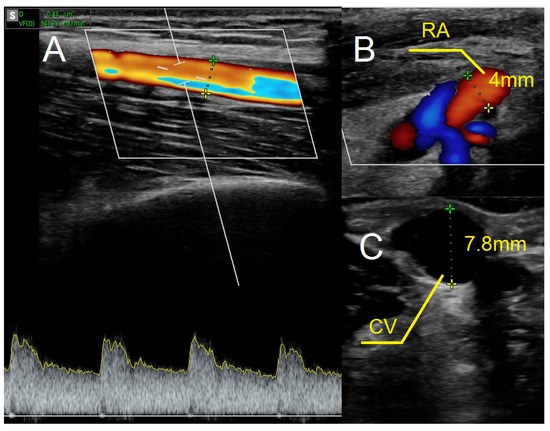

Figure 6.

Ultrasound examination after creating the fistula using the RADAR technique. (A) Fistula flow measured on brachial artery. (B) Doppler ultrasound—a longitudinal section of the radial artery. (C) The cephalic vein in cross-section at the cubital fossa. Abbreviations: RADAR—radial artery deviation and reimplantation, RA—radial artery, CV—cephalic vein.

As in previous cases, the surgical site was determined by the results of the ultrasound examination. In the present case, the patent artery was found in the third proximal of the forearm (Figure 5A). The procedure was carried out as described above. In this case, however, the vein and artery were in close proximity to one another, which is why Option II for anastomosis was chosen. After performing an anastomosis and releasing the clamps, we detected a blood flow in the vessel (Figure 5B). The following day’s ultrasound examination of the fistula revealed a flow rate of 541 mL/min (Figure 6A). The diameter of the radial artery (Figure 6B) and the cephalic vein (Figure 6C) also increased to 4 mm and 7.8 mm, respectively. The patient was given salicylic acid in the postoperative period, despite having taken this medication prior to creating a fistula due to antiphospholipid syndrome. One month later, the fistula was successfully cannulated.